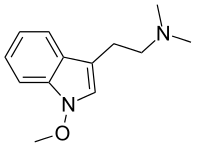

| Lespedamine | Plants | 1-OCH3 | CH3 | CH3 | 1-methoxy-N,N-dimethyltryptamine | 4335-93-7 |